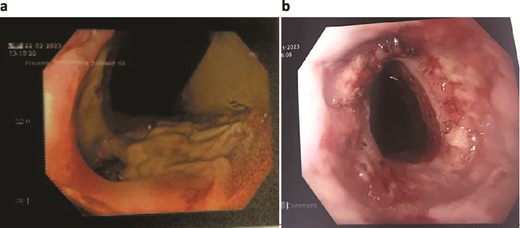

On day 2 post-diagnosis, the patient underwent an OGD, VACStent insertion, and ultrasound-guided pleural drain placement. The endoscopy revealed a 2 cm linear defect in the lower oesophagus just above the gastroesophageal junction (Fig. 3), and the VACStent was connected to 125 mmHg of negative pressure, confirming appropriate positioning. The patient tolerated the procedure well without intraoperative complications and was transferred to the ICU intubated.

Patient Three: Before VACStent insertion, showing the oesophageal defect.